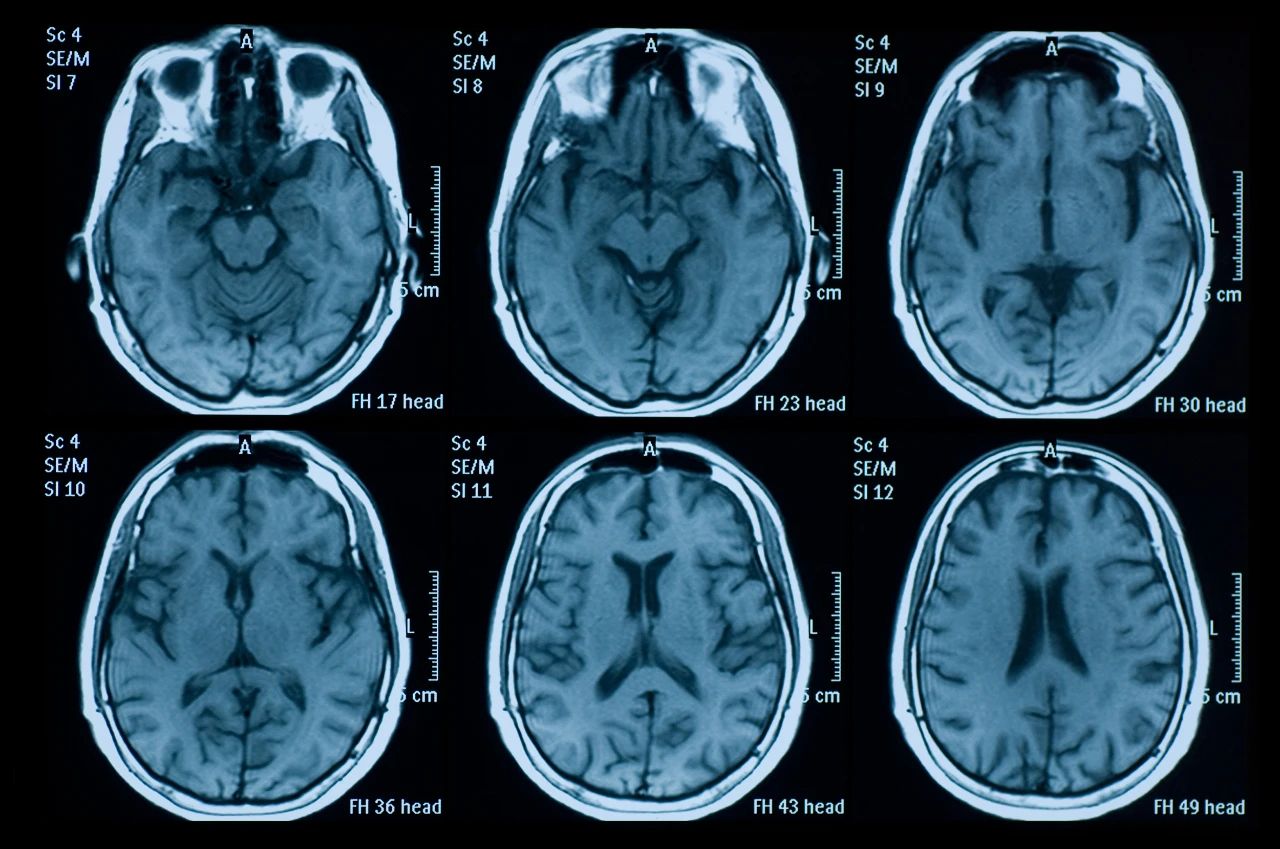

什么是創傷性腦損傷?

頭部受傷是頭部受到撞擊。它可能是輕微的,導致小腫塊或瘀傷,也可能更嚴重,導致腦損傷,如腦震蕩或腦出血。